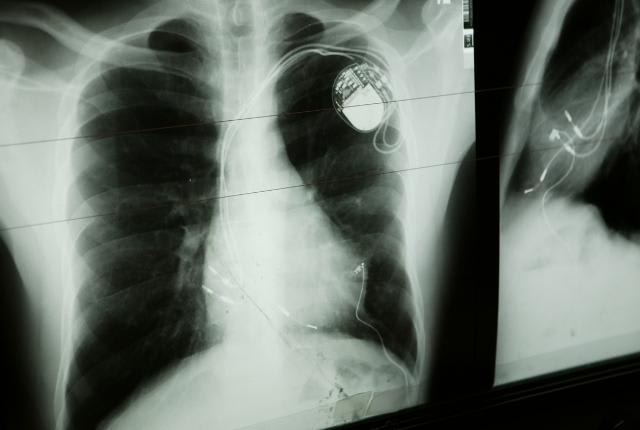

Un pacemaker, également appelé stimulateur cardiaque ou pile cardiaque, est, comme son nom l'indique, un dispositif médical implanté dans le corps humain ayant pour but de délivrer des impulsions électriques régulières au myocarde (tissu musculaire du cœur) et de stimuler ainsi les contractions des muscles à un rythme régulier. Il peut délivrer une impulsion électrique pendant plusieurs années grâce à une batterie. Ce pacemaker pour le cœur habituellement implanté sous la clavicule est donc utile pour surveiller l'activité cardiaque naturelle, ainsi que pour traiter les troubles du rythme cardiaque (arythmie cardiaque) , tels que la bradycardie par exemple (fréquence cardiaque anormalement lente), et leurs conséquences.

Un pacemaker cardiaque est un appareil composé d'un boîtier d'environ 4 centimètres – contenant notamment la batterie – et de sondes reliant le boîtier aux cavités cardiaques. L'implantation d'un pacemaker est généralement réalisée sous anesthésie locale et ne nécessite donc pas d'opération à cœur ouvert.

L'implantation d'un stimulateur cardiaque est souvent réalisée sous anesthésie locale, voire générale, et ne requiert donc généralement pas d'opération à cœur ouvert. Elle consiste en une incision en haut de la poitrine, sous la clavicule, et ce afin d'insérer les sondes jusqu'aux cavités cardiaques, puis le boîtier contenant notamment la batterie.